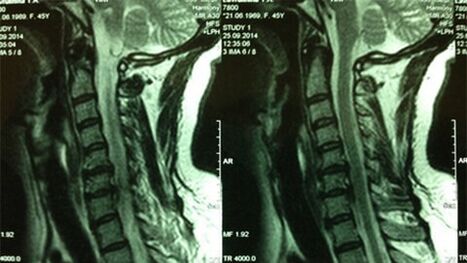

- X -yoga of the cervix class;In the initial stages of the process, the MRI of the Cervical Class will be more informative - which ensures high quality display of solid and soft tissues - shows the condition of intervertebral discs, the presence of osteophytes, deformations, and nerve root damage;evaluates the condition of tapes, muscles, bone tissue;